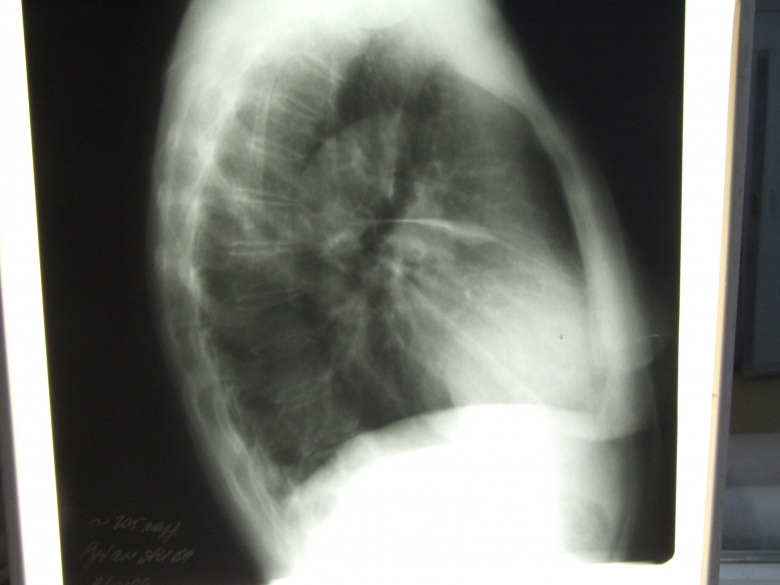

Жидкость в междолевой борозде. После перенесенного плеврита образовались спайки. Вывод подтвержден (увы) вскрытием.